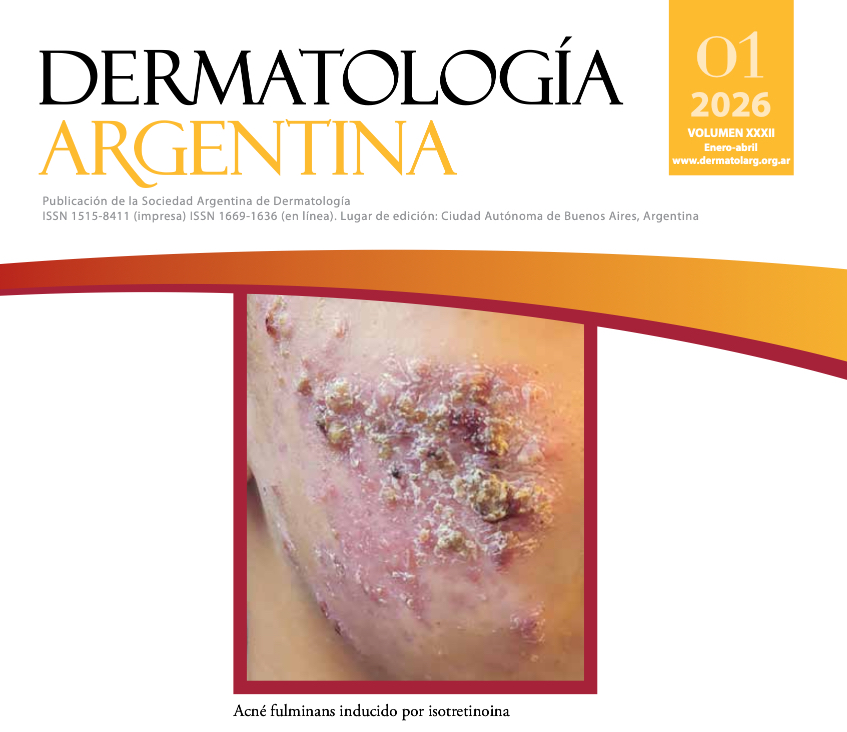

TRABAJO ORIGINAL. Acné fulminans inducido por isotretinoína

Rabanal F y col.

El acné fulminans (AF) es una forma clínica severa de acné inflamatorio caracterizado por un brote súbito y doloroso de nódulos, pápulas, pústulas hemorrágicas y úlceras con costras en la cara y el tronco superior. Puede o no estar asociado a síntomas sistémicos y alteraciones en el laboratorio. Afecta más frecuentemente a adolescentes de sexo masculino con antecedente de acné.

En este artículo, los autores presentan cinco casos de AF inducido por isotretinoína, en su mayoría sin síntomas sistémicos asociados. En todos los casos, el diagnóstico se estableció a partir de los hallazgos clínicos, los antecedentes del paciente y los exámenes complementarios.

Todos los pacientes recibieron tratamiento sistémico; sin embargo, el manejo terapéutico se individualizó según el criterio del médico tratante y la disponibilidad de recursos. En la actualidad no existen esquemas terapéuticos completamente estandarizados para esta entidad.

Pápulas y nódulos eritematosos cubiertos por costras necróticas en el tórax